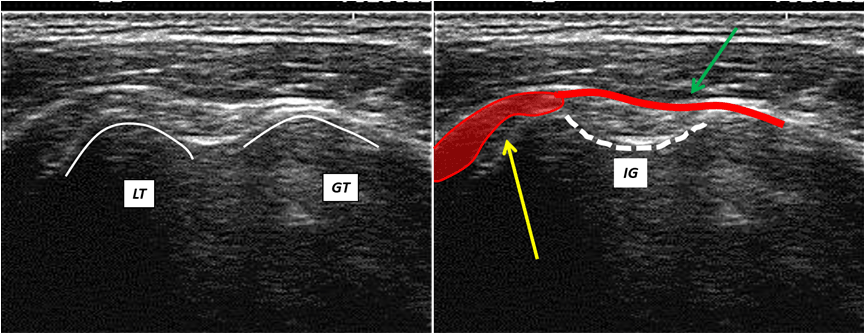

The ultrasound transversal view can be classified into four types (Figures 1,2,3,4).

Figure 4: Ultrasound transversal view Type IV: The fibers (yellow arrow) of the SCM tendon are attached to the lesser tubercle by means of aponeurotic fibers (green arrow), extend as far as the greater tubercle, running above the IG; LT = lesser tubercle; GT = greater tubercle; IG = intertubercular groove.